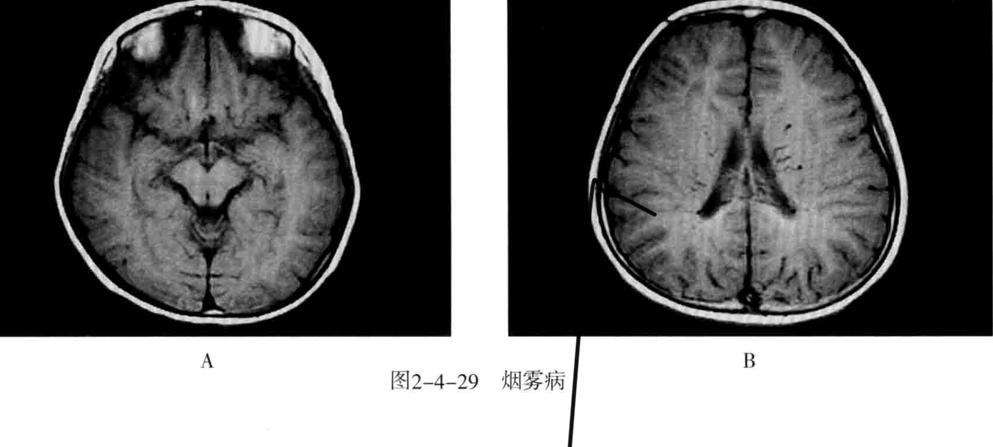

十、烟雾病

又称为脑底异常血管网症、脑底动脉环闭塞症。是以脑内虹吸段至大脑前、中动脉近端狭窄或闭塞,同时伴有广泛侧支循环形成,导致颅底出现异常毛细血管网为特征的脑血管病。好发年龄10岁以下和40-50岁。临床表现为脑缺血和脑出血两大类。儿童多为颈内动脉系统缺血性改变,成人多为颅内出血。

- CT平扫表现为双侧额叶、顶叶及颞叶皮质或皮质下区多发脑梗死及脑萎缩改变,也可以出现颅内出血。增强有时可见到颈内动脉及大脑前中动脉粗细明显不对称,或者充盈不良,甚至不显影。可显示基底池及基底节区的侧支循环网,大多表现为为不规则的扭曲成团的强化血管影。

- MRI表现为脑缺血引起的T1WI低、T2WI高信号脑梗死区,颈内动脉及大脑中动脉主干的“流空效应”变弱或消失,异常血管网在T2WI上表现为基底节区和鞍上池内多发细小血管影,呈网状低信号或无信号区。皮质侧支循环形成时,增强扫描可见皮质血管增多、扩张、强化、呈“常春藤征”。

- MRA可直接显示颈内动脉、大脑前、中动脉狭窄或闭塞,于颅底见烟雾状异常血管网,常可见到颈外动脉和椎-基底动脉分支代偿性增粗。

- 脑血管造影是确诊烟雾病的主要检查方法,可显示狭窄或闭塞的动脉及异常扩张的血管网。